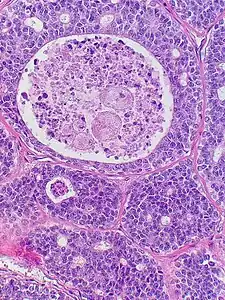

| Micrograph of an adenoid cystic carcinoma of a salivary gland (right of image): Normal serous glands, typical of the parotid gland, are also seen (left of image), H&E stain. | |

Histopathological image of adenoid cystic carcinoma of the salivary gland infiltrating a nerve (center), H&E stain

Adenoid cystic carcinoma with comedonecrosis